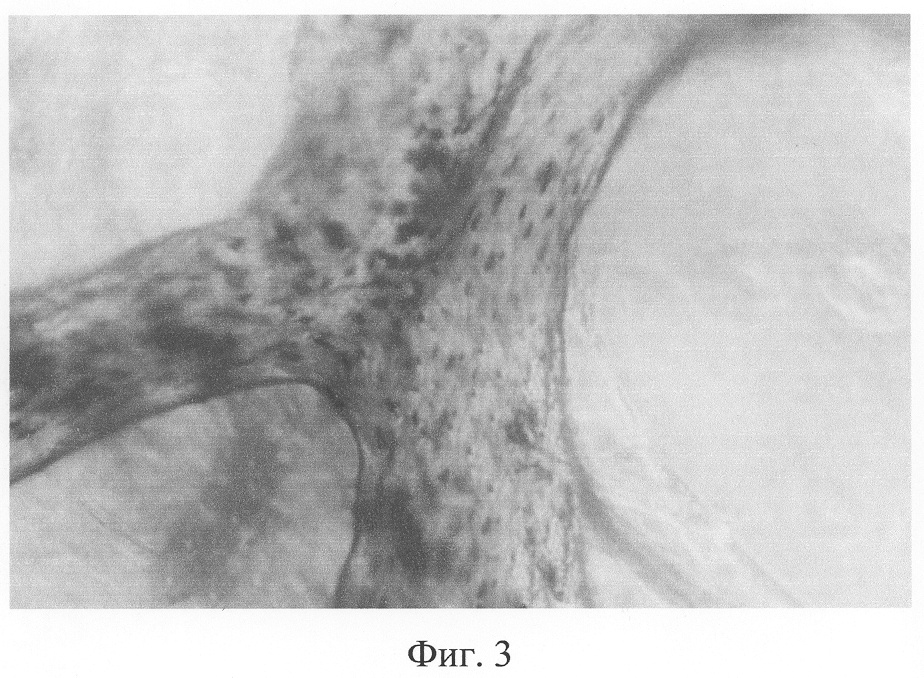

Из костного мозга пациента выделяют аутологичные мезенхимные стволовые клетки фенотипа: CD 34-; CD 45-; CD 44+; CD 90+; CD 105+; CD 106+. Биотрансплантат из ДКТ и выделенных МСК готовят заранее. В лабораторных условиях ДКТ отмывают в растворе Хенкса в течение 24-48 часов, что обеспечивает РН среды для дальнейшей работы с жизнеспособным клеточным материалом, и помещают в среду с аутосывороткой. На трансплантат наносится суспензия подготовленных аутологичных мезенхимных стволовых клеток. Заселение трансплантата клетками проводят до достижения необходимой плотности клеток в 1 см3, т.е. оптимальной плотности заселения для получения очагов костеобразования. Заселение трансплантата производится в течение 24-72 часов (в зависимости от размеров трансплантатов от 15 до 40 см3) с плотностью 7-10 млн на 1 см3 трансплантата (фиг.3-4).